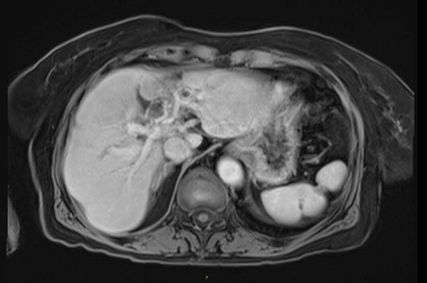

In der durchgeführten Staging-CT zeigte sich ein partielles Ansprechen (PR) mit Tumorgrößenreduktion von 49mm auf 33mm, die Lymphknoten blieben unverändert. Die Tumormarker sanken (AFP: 150, Ca19-9: 65). Aufgrund der persistierenden Diarrhö und des Verdachts auf einen Mischtumor erfolgte eine Umstellung der Therapie auf Cisplatin/Gemcitabin/Bevacizumab, wobei Gemcitabin ab Zyklus 2 wegen Fatigue auf 75% reduziert wurde und Cisplatin ab Zyklus 3 aufgrund von Ototoxizität abgesetzt werden musste. Nach vier Zyklen zeigte die MRT ein weiteres partielles Ansprechen (19×21mm), die Lymphknoten waren unverändert, die Tumormarker normalisierten sich erstmals.

Bildgebend können sich Mischtumoren wie ein HCC-iCCA-Gemisch imponierend darstellen, wie ein typisches HCC oder aber ein typisches iCCA aussehen oder sich unspezifisch darstellen. Bildgebende Hinweise auf Mischtumoren bestehen bei verschiedenartigem Kontrastmittelverhalten innerhalb eines Tumors (im Verlauf zunehmende Anreicherung, Anreicherung mit Wash-out, Anreicherung ohne Wash-out oder Hypovaskularisierung), vaskulärer Invasion und Gallengangsbeziehungen. Die Kombination erhöhter Tumormarker (AFP und Ca19-9) kann einen Hinweis liefern, ist aber nicht beweisend.